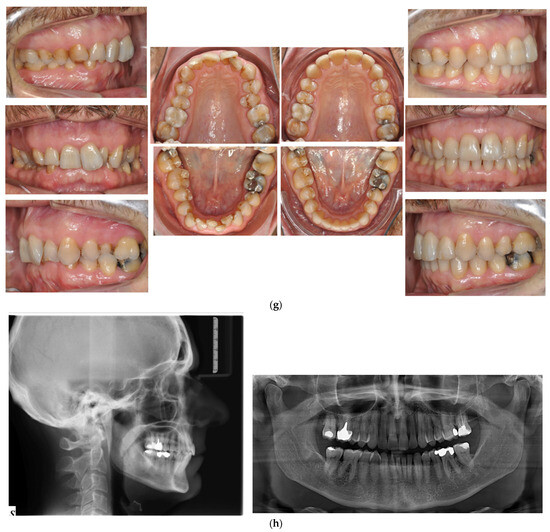

- Case 1: Class II division 2 with deep bite

4.1. Case 1: Class II Division 2 with a Deep Bite